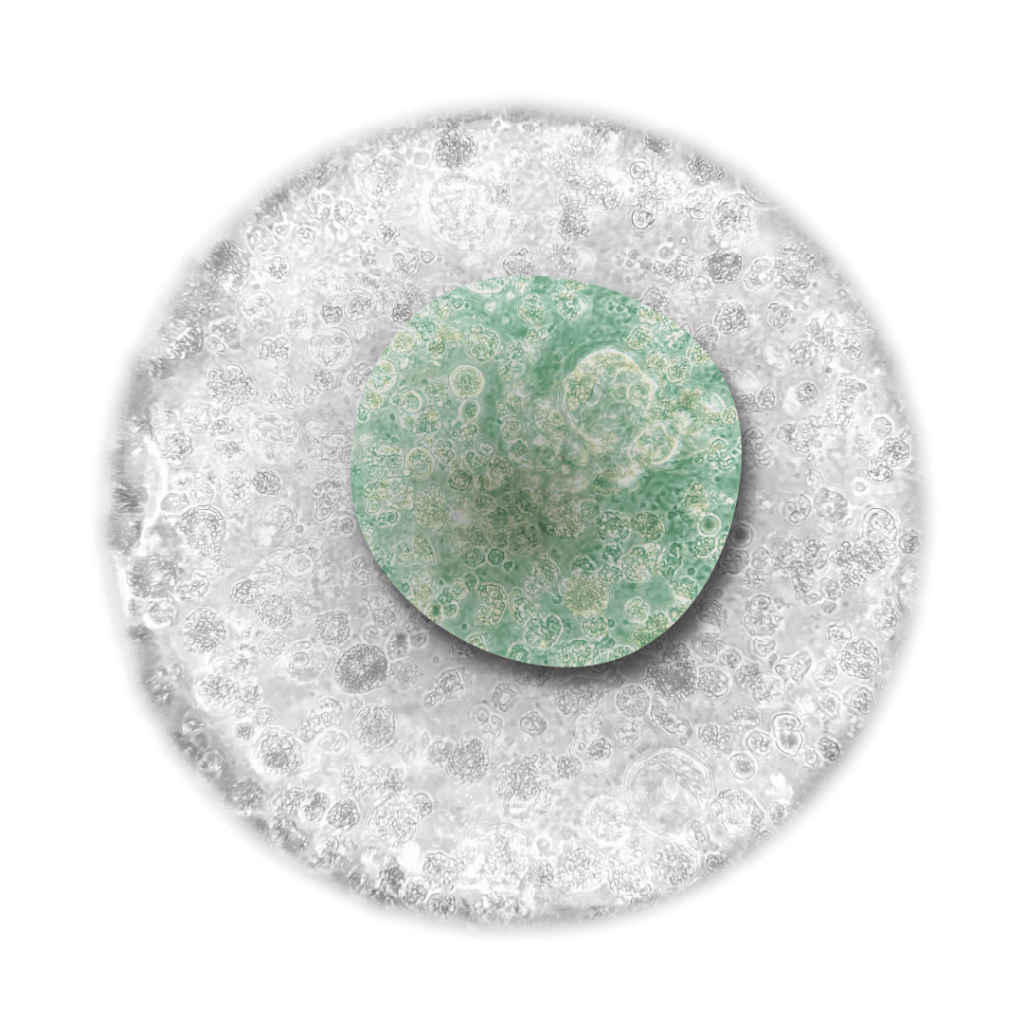

La profilazione genica è un processo che analizza il DNA tumorale per individuare specifiche mutazioni genetiche e alterazioni che possono influenzare la progressione della malattia e la risposta ai trattamenti.

La profilazione genica permette di adattare la terapia oncologica alle caratteristiche uniche del tumore di ciascun paziente in questo modo parliamo di Personalizzazione del Trattamento.

L’integrazione della biopsia liquida e della profilazione genica segna un importante passo avanti nella medicina oncologica di precisione, permettendo un approccio diagnostico e terapeutico sempre più personalizzato, tempestivo e mirato.